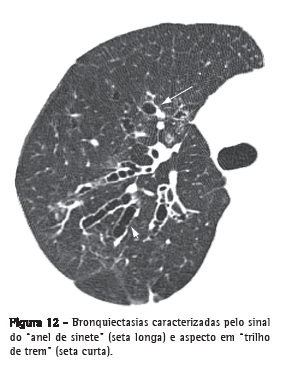

Bronquiectasia

Dilatação brônquica irreversível, que pode ser focal ou difusa. Geralmente decorre de infecção crônica, obstrução das vias aéreas proximais ou anormalidades brônquicas congênitas. Os achados morfológicos na TCAR (Figura 12) incluem o diâmetro interno do brônquio maior do que o da artéria pulmonar adjacente (sinal do anel de sinete); a perda do afilamento gradual do brônquio, definido como a manutenção do calibre por mais que 2 cm, distal à bifurcação (aspecto em "trilho de trem"); e a identificação de via aérea a menos de 1 cm da superfície pleural.

Bronquiectasias são frequentemente acompanhadas de espessamento das paredes brônquicas, impacção mucoide e alterações de pequenas vias aéreas.(26,27) A patologia define três tipos de bronquiectasia, a depender da aparência do brônquio acometido: cilíndrica, varicosa e sacular (ou cística).

Ver também Sinal do anel de sinete.

Sinal do anel de sinete

Sinal composto por uma opacidade anelar, que representa um brônquio dilatado, em associação com uma opacidade arredondada menor, contígua a sua parede, representando sua artéria (pulmonar ou raramente brônquica) que lembra o aspecto de um "anel de sinete" ou "anel de pérola".(74) Corresponde ao sinal tomográfico básico de bronquiectasia (Figura 12).(26,75) Ocasionalmente, o sinal do anel de sinete pode também ser encontrado em doenças caracterizadas por uma redução anormal do fluxo arterial pulmonar, tais como no tromboembolismo pulmonar crônico e na interrupção proximal da artéria pulmonar.(76)

Ver também Bronquiectasia.